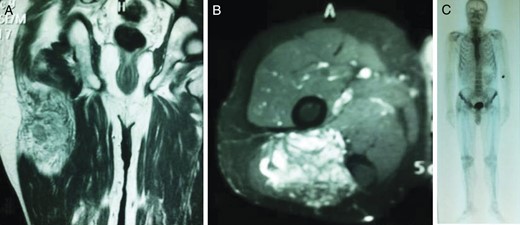

A 67-year-old man was admitted to our orthopedic clinic for a painful hard mass that had been slowly growing for >1 year at the posterolateral aspect of the right thigh. He had a 9-year history of left radical nephrectomy for a 6-cm diameter RCC (stage II [pT1 N0 Mx], nuclear grade Fuhrman grade III/IV). On physical examination, a 10 × 7 cm palpable mass was detected at the right posterolateral gluteal region. Magnetic resonance imaging (MRI) revealed a 165 × 75 × 67 cm hypervascular lesion within the gluteus maximus muscle, with unclear borders to the biceps femoris (Fig. 1A and B). After an incisional biopsy, the mass was reported as an RCC metastasis (Fig. 2A and B). Total excision of the mass was performed. Histochemical analysis of the total excision specimen revealed positive staining for cytokeratin, RCC and vimentin confirming the diagnosis. We performed a total body bone scan (Fig. 1C) to achieve complete stadiation of the mass. After complete healing, external radiotherapy was administered at 30 Gy to the right leg, in the surgical site, with an additional three cycles of immunotherapy regimen, including interferon-α (IFN-α), interleukin 2 and sunitinib therapy.

Coronal (A) and axial (B) T2-weighted fat-suppressed images showing the encapsulated soft tissue mass within the right gluteus maximus muscle; (C) whole-body bone scintigraphic image.